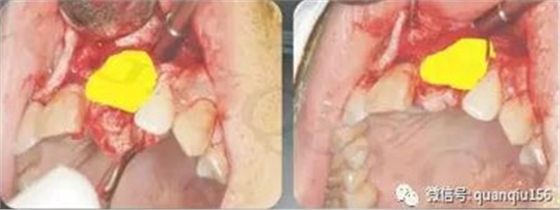

一、種植牙植骨第一個步驟:切口從上頜尖牙到第一磨牙齦頰溝橫行切口,切開粘膜、骨膜,分離翻起粘骨膜瓣,顯露上頜竇外壁骨面,勿傷及眶下神經(jīng)。相關(guān)文章:牙齦萎縮能種植牙嗎

二、種植牙植骨第二個步驟:在骨面上按竇腔大小用直徑2mm球鉆開一矩形窗口。鉆孔時只穿透骨壁,勿損傷粘膜。

三、種植牙植骨第三個步驟:分離上移骨粘膜瓣自上頜竇底起始,用一彎度適宜的鼻粘膜剝離子貼骨壁仔細分離、上推竇粘膜直至植骨的高度,一般上移1.5cm即可。竇膜很薄,平均只有0.1mm左右,就像氣球很容易破裂,一旦破裂直接影響手術(shù)效果。上頜竇黏膜穿孔的原因主要在于黏膜狀況及手術(shù)操作。

四、種植牙植骨第四個步驟:植入人工骨粉,蓋口腔修復(fù)膜,如骨膜完整也可以不蓋膜。

五、種植牙植骨第五個步驟:如果同期種植,沿齦頰溝切口向腭側(cè)分離翻轉(zhuǎn)粘骨膜瓣,顯露牙槽嵴骨面,在設(shè)計的位置上逐級鉆孔,最后將種植體旋入就位。術(shù)前骨高度嚴(yán)重不足的也可以半年后種植。